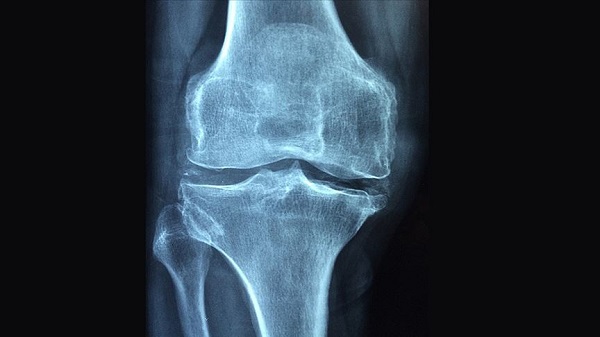

Uzm. Dr. Şeyma Büyükkömürcü, “Boyda kısalma ve kamburluk, alçak mesafeden travmasız veya çok az bir travma ile olan düşmelerde bile kemiklerin kırılması, omurgada kemik yoğunluğunun azalması sonucu oluşan çökme kırıklarına bağlı sırt ve bel ağrıları, iç organların sıkışmasına bağlı solunum ve kalp fonksiyon bozuklukları gibi belirtiler, osteoporozu işaret eder” dedi.

Osteoporoz tanısının detaylı bir muayene, kemik yoğunluğu ölçümü (kemik dansitometresi) ve omurga kırıkları açısından görüntüleme yöntemleri ile konulduğunu belirten Uzm. Dr. Şeyma Büyükkömürcü, “65 yaş ve üzeri bütün kadınların ve 70 yaş ve üzeri bütün erkeklerin kemik taraması yaptırmalıdır; ayrıca kırık risk faktörlerinden en az 1 tanesine sahip olan 65 yaş altı menopoz sonrası dönemde olan kadınlar ile 50-69 yaş arası erkeklerin de kemik taraması yaptırması önerilmektedir” diye konuştu.